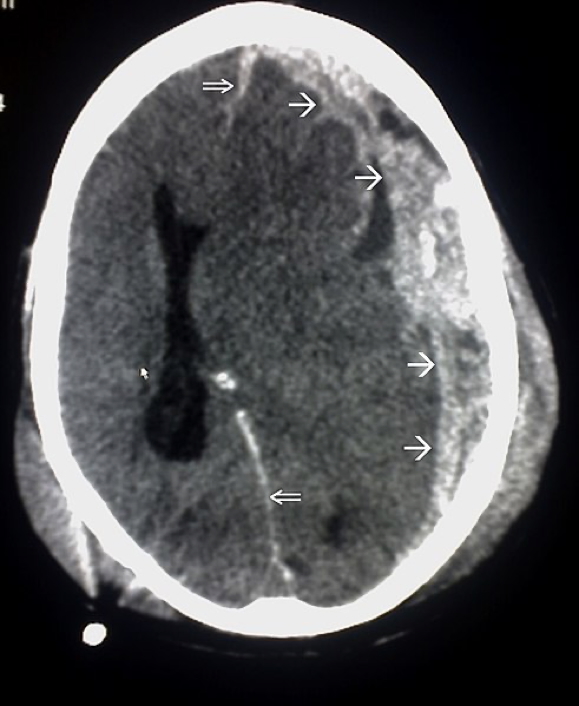

Intracerebral Haemorrhage

Aetiology

- Hypertension (most common)

- AV malformations, trauma, bleeding diathesis

Pathogenesis

- Bleeding into brain parenchyma

- Leads to mass effect, ↑ICP, and ischaemia

Morphology

- Slit haemorrhages in chronic HTN

- Lacunar infarcts in brainstem/basal ganglia

Clinical Features

- Acute headache, vomiting, meningism

- Nystagmus, anisocoria, focal neurological deficits

- Signs of raised ICP and possible brain herniation

- Altered consciousness

Investigations

- CT/MRI Brain: Confirms haemorrhage

- Transcranial Doppler: Assess AVMs